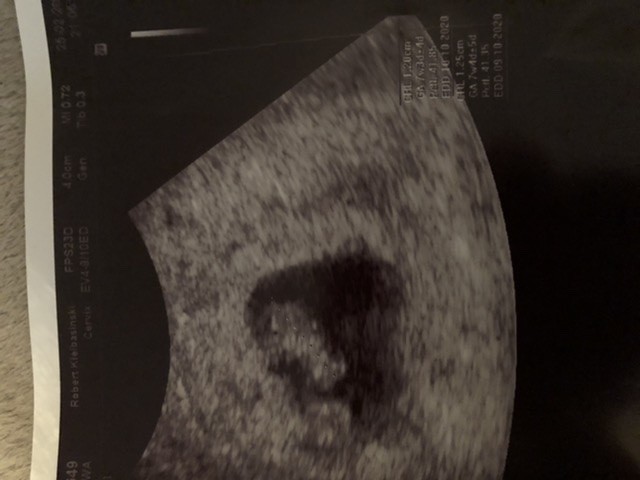

Super [emoji173][emoji173][emoji173]Zobacz załącznik 1084949

[emoji3590] Ślicznie pika - 148 [emoji846] 1,23 cm. Termin na 10.10, 7t 3d [emoji16][emoji16][emoji16][emoji16][emoji16]